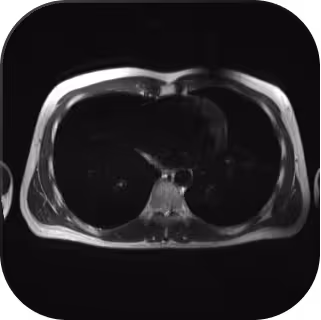

Our MRI scans do not use any radiation at all. They rely on magnetic fields and radio waves, making them completely safe and free from ionising radiation.

CT scans do involve a small amount of radiation, but at Everlab we use ultra low-dose protocols. The exposure is extremely low — less than what you naturally receive over a few months just living on Earth, and often lower than the radiation from a long-haul flight.

- Ultra-Low-Dose CT Chest (non-contrast)

A quick scan that takes 5–10 minutes, with a short breath-hold. There are no needles or contrast dyes, and it's over quite fast. - Whole-Body MRI (no contrast)